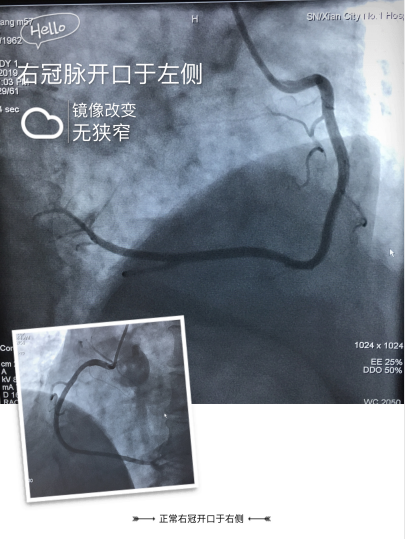

面对首例右位心冠脉造影手术,为保障手术顺利、安全进行,我科赵朝主任召集心血管病医院程曼丽院长等医务团队开展术前讨论,就手术中可能遇到的问题制定解决方案,1如果常规的冠脉造影导管不能顺利完成,那么需要准备特殊类型的造影导管,2若病情需要支架置入治疗,可能需要准备特殊耗材,如Amplatz Right1.0、Amplatz Left1.0、XB Right 1.0、XB Right 1.0、Extra Rackup Right1.0等;充分的准备后,于2019-09-04由心内三赵朝主任,陆艳副主任医师带领团队行右位心冠脉造影术,术中通过JR4.0造影导管在左冠状窦内找到右冠状动脉开口,造影显示血管光滑无狭窄。以JL4.0造影导管在右冠窦内找到左冠状动脉开口,造影显示血管光滑无狭窄。明确排除了患者冠心病诊断,治疗做出相应调整,考虑症状可能与冠脉痉挛等功能性改变引起,积极加强改善痉挛、改善心肌代谢、改善症状治疗。排除冠心病并给予适当的心理疏导后,患者症状逐渐减轻出院。我科在充分的准备工作后,顺利完成了首例右位心的冠脉造影术,积累了宝贵的手术经验,保障了患者生命安全。